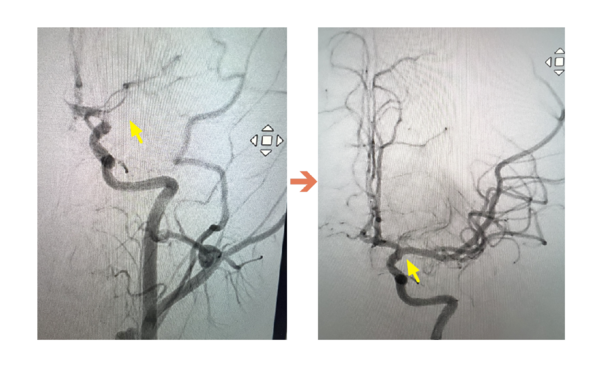

▲ICA血管攝影,圖左箭頭處為血栓阻塞血管,圖右箭頭處為已打通血管。(圖/聯新國際醫院提供)

這名國中生被送往聯新國際醫院急診室救治時,神經內科李振華醫師透過電腦斷層影像掃描,檢查結果確定為左側中大腦動脈栓塞造成缺血性腦中風,與家屬充分溝通後,影像醫學科主任暨取栓醫師郭葉璘隨即與取栓團隊進行急性腦中風顱內動脈血栓移除(Intra-arterial thrombectomy, IAT),從腹股溝導引導管至左側中大腦動脈阻塞處,採用強力抽吸方式清除血栓。手術從開始到打通血管僅花費約10分鐘,成功取出4個血栓,其中最大達1.1公分,患者術後血流恢復暢通。